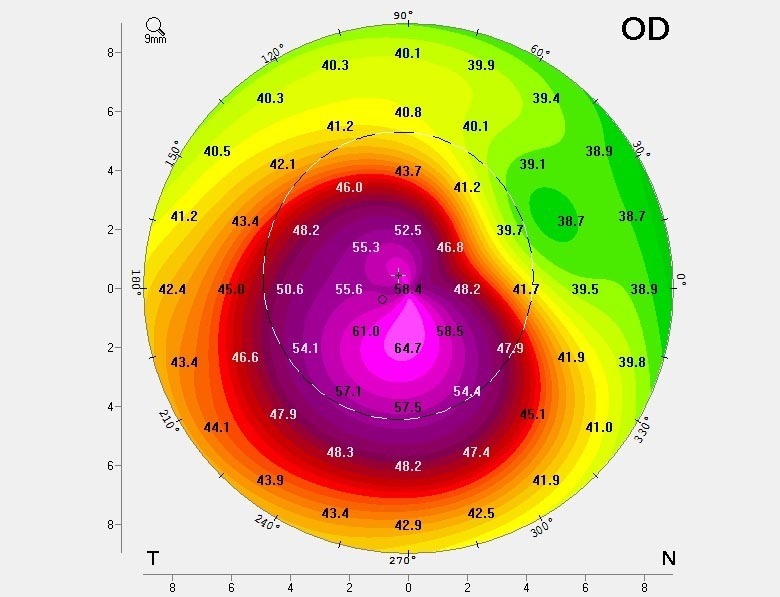

Diese Hornhaut ist erkrankt und benötigt weitere Untersuchungen/Behandlungen. Man erkennt, dass die Hornhaut im oberen Anteil flach ist und im unteren Anteil sehr stark vorgewölbt. Die Sehkraft ist verzerrt, es bestehen Doppel- oder sogar Dreifach- und Vierfach-Bilder und in vielen Fällen kann auch eine Brille die Sehschärfe nicht mehr wiederherstellen. Zudem ist die Krankheit fortschreitend und kann vor allem bei Kindern und Jugendlichen bis zu schwersten Sehbehinderungen führen.

Dank neuester Technologien sind wir heute in der Lage, sowohl die vordere als auch die hintere Oberfläche der Hornhaut mit extrem hoher Präzision zu messen. Dank dieser verbesserten Genauigkeit können Anomalien bereits in sehr frühen Stadien erkannt werden, was zu schnelleren und zuverlässigeren Diagnosen führt. Erkrankungen wie Keratokonus oder Pellucid Marginal Degeneration (PMD) lassen sich nun deutlich früher als bisher diagnostizieren, was die Patientenergebnisse verbessert und eine rechtzeitige Behandlung ermöglicht.